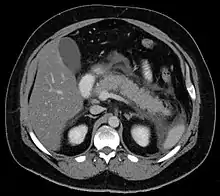

For imaging, abdominal ultrasound is convenient, simple, non-invasive, and inexpensive.[32] It is more sensitive and specific for pancreatitis from gallstones than other imaging modalities.[30] However, in 25–35% of patients the view of the pancreas can be obstructed by bowel gas making it difficult to evaluate.[29]

A contrast-enhanced CT scan is usually performed more than 48 hours after the onset of pain to evaluate for pancreatic necrosis and extrapancreatic fluid as well as predict the severity of the disease. CT scanning earlier can be falsely reassuring.